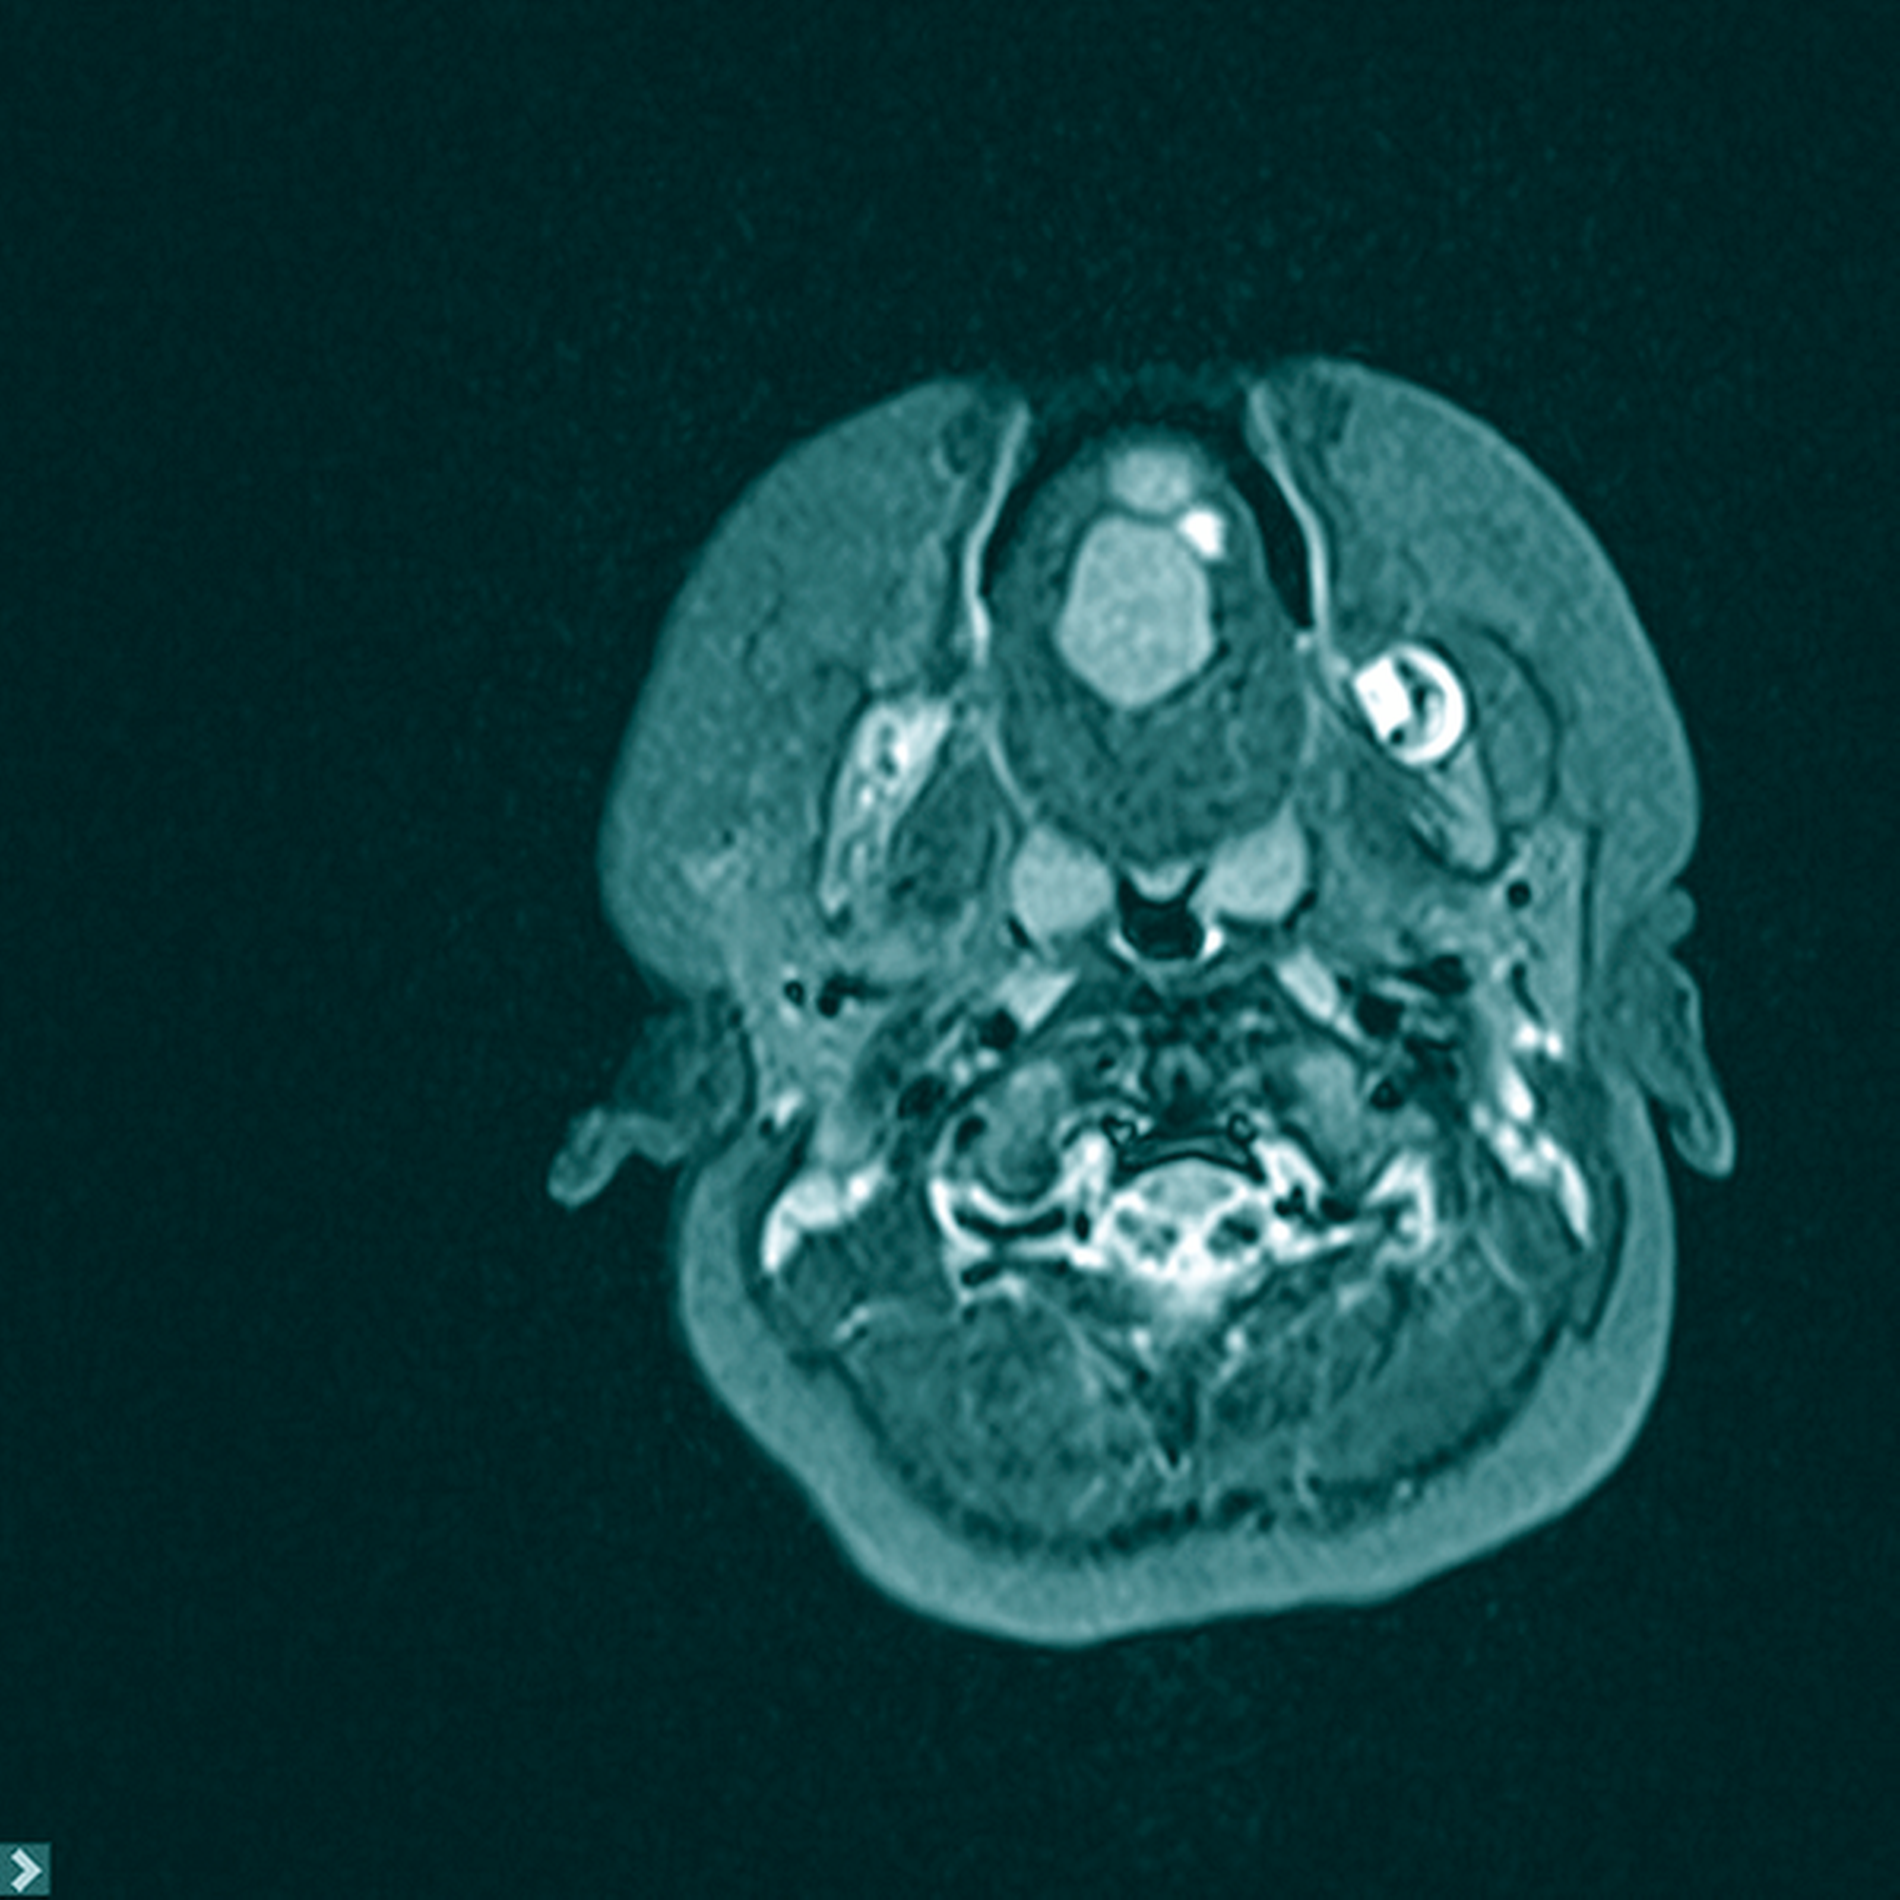

Zur erweiterten Diagnostik wurde in Sedierung eine Magnetresonanztomografie durchgeführt. Hier zeigten sich im Bereich des Zungenkörpers mit Übergang auf den Mundboden mehrere, konglomerierende zystische Läsionen (T1w nativ: flau hyperintense, Abbildung 2; T2w: hyperintense, teils diffusionsrestringiert, Abbildung 3) mit einer Gesamtausdehnung von 3,0 cm x 2,5 cm x 2,2 cm. Bildmorphologisch bestand der Verdacht auf eine Dermoid-Zyste, eine Foregut-Zyste oder ein zystisches Lymphangiom.